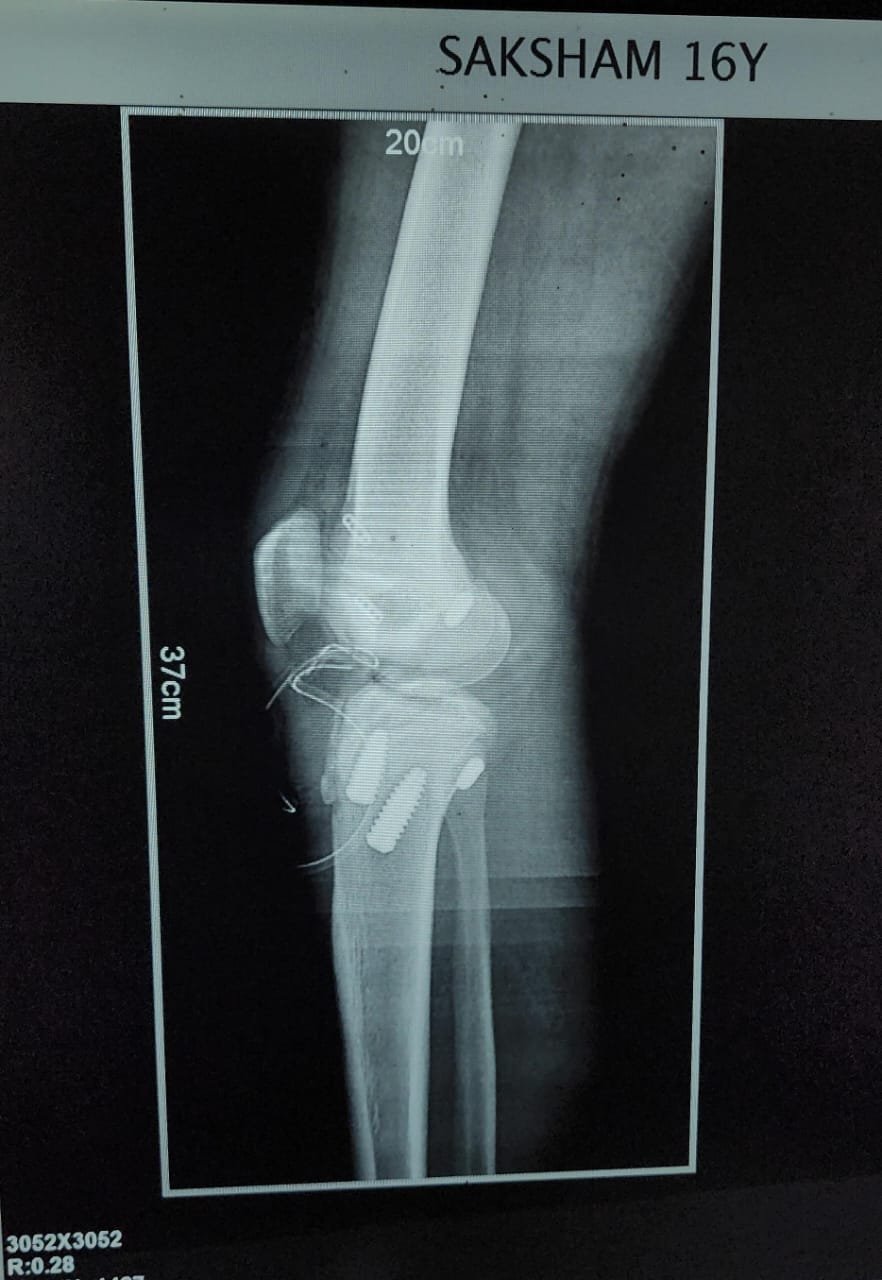

Orthopaedic Surgeon | Arthroscopy & Joint Replacement Specialist

Dr. Aditya Tripathi is a dedicated and skilled Orthopaedic Surgeon specializing in sports injuries, arthroscopy, and joint care. Known for his clinical precision, ethical practice, and patient-first approach, he focuses on helping patients regain mobility, strength, and confidence through evidence-based orthopaedic treatment. His academic background and hands-on clinical training reflect a strong foundation and a commitment to excellence in orthopaedic care.

Dr. Aditya Tripathi is widely appreciated by patients for his clear communication, honest medical guidance, and personalized treatment approach. His expertise in managing ACL tears, ligament injuries, shoulder conditions, and sports-related injuries makes him a trusted choice for comprehensive orthopaedic and sports injury care. Patients value his attention to detail, compassionate care, and focus on long-term recovery—establishing him as a reliable and respected orthopaedic specialist.

Specialization And Expertise

- Sports Injuries

- Robotic Joint Replacement

- ACL Reconstruction

- PCL Reconstruction

- Meniscus Repair

- Arthroscopy-Knee

- Arthroscopy-Shoulder

- Knee Replacement Surgery

- Hip Replacement Surgery

- Shoulder Replacement Surgery

- Fracture Treatment